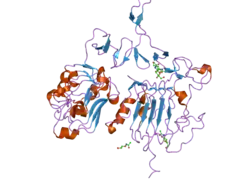

HER2 is the target of the monoclonal antibody trastuzumab (marketed as Herceptin). Trastuzumab is effective only in cancers where HER2 is over-expressed. One year of trastuzumab therapy is recommended for all patients with HER2-positive breast cancer who are also receiving chemotherapy.[33] Twelve months of trastuzumab therapy is optimal. Randomized trials have demonstrated no additional benefit beyond 12 months, whereas 6 months has been shown to be inferior to 12. Trastuzumab is administered intravenously weekly or every 3 weeks.[34]

An important downstream effect of trastuzumab binding to HER2 is an increase in p27, a protein that halts cell proliferation.[35] Another monoclonal antibody, Pertuzumab, which inhibits dimerisation of HER2 and HER3 receptors, was approved by the FDA for use in combination with trastuzumab in June 2012.

Among approved anti-HER2 therapeutics are also tyrosine kinase inhibitors (such as lapatinib, neratinib, and tucatinib) and antibody-drug conjugates (ado-trastuzumab emtansine and trastuzumab deruxtecan).[40]